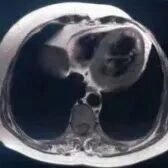

阜外医院宋雷、崔成教授高血栓负荷编织样血管PCI治疗一例